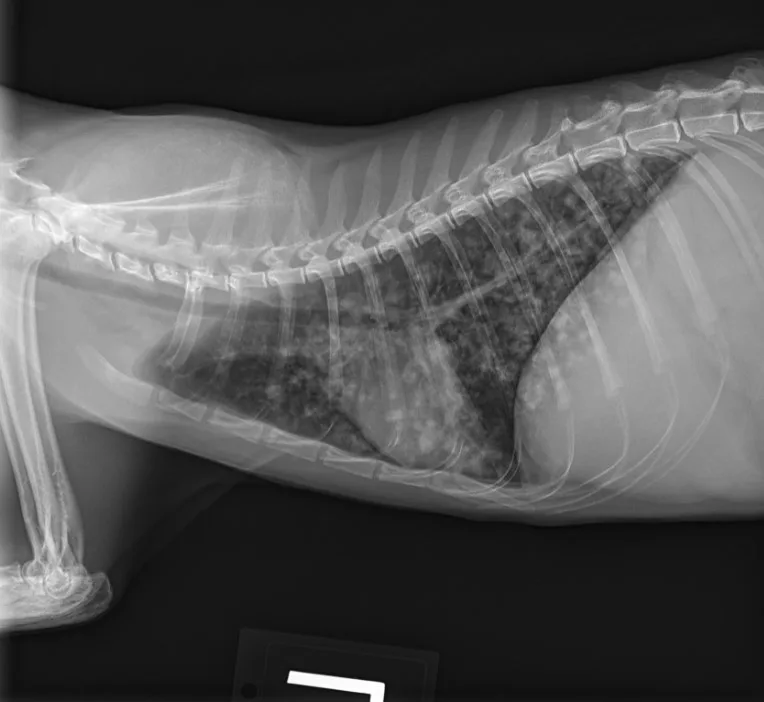

This case-based review explores the diagnostic approach to infectious pneumonia in cats and outlines practical therapeutic considerations for achieving clinical resolution in cases of pneumonia caused by Histoplasma capsulatum.